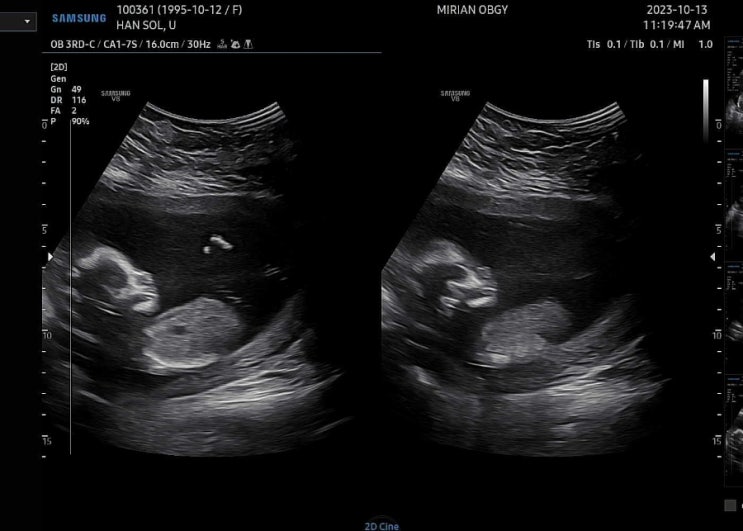

[임신33주~35주]실제로 느낌 임신 주수별 증상 및 초음파사진 : 후기 (막달검사)

안녕하세요~ 솔나무입니다 오늘은 임신 33주~35주차까지의 증상들을 작성해보려고 합니다 중기때는 시간이 ...